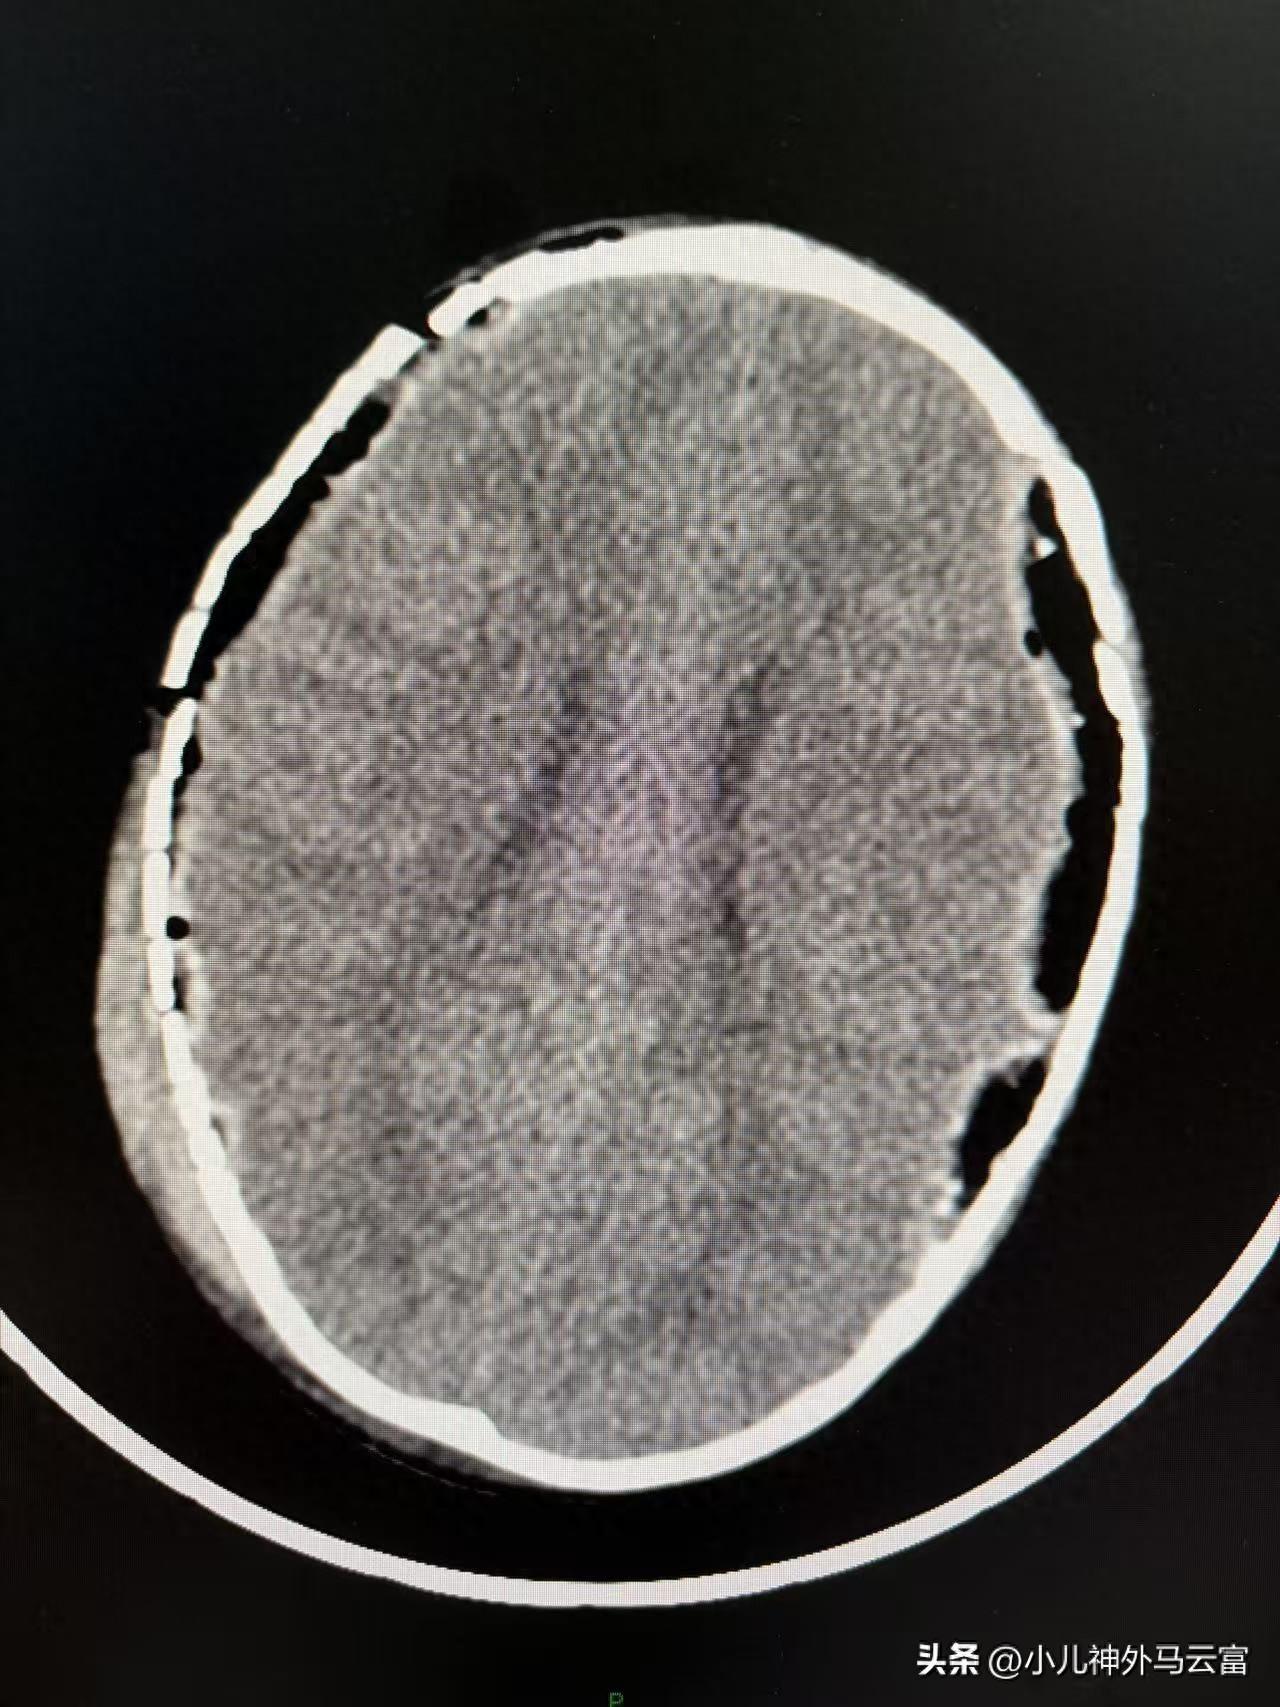

【基本信息】男,11個月

【疾病類型】顱縫早閉(矢狀縫),舟狀頭

【治療方案】顱縫再造術

【治療效果】手術順利,目前恢復良好

術後影像、照片: